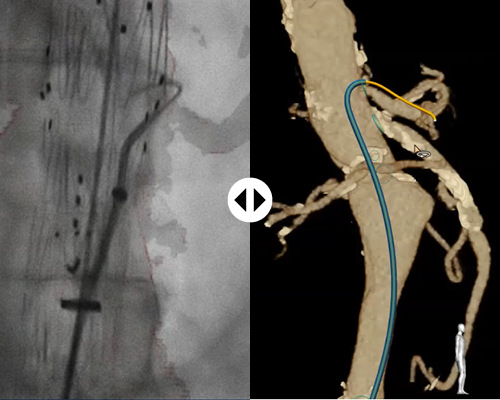

Fiber Optic RealShape (FORS) technology sparks a new era in device guidance. Using the wonders of light, this unique innovation, exclusive to Philips, enables real-time, 3D visualization of devices* inside the body. Without the need for fluoro!

FORS- enabled guidewires have a hair-thin optical fiber integrated into them. By pulsing light into the fiber and analyzing how it is reflected, the full shape of devices can be reconstructed and visualized. These devices are shown in the context of the patient’s anatomy through overlay on images that are acquired before or during the procedure, like CT scans and X- rays.

FORS technology makes it possible to display the full shape of devices in 3D and in distinctive colors, as opposed to the 2D, greyscale visualization produced by fluoroscopy. FORS images are generated in real-time, and can be rotated and tilted to allow viewing from any angle.